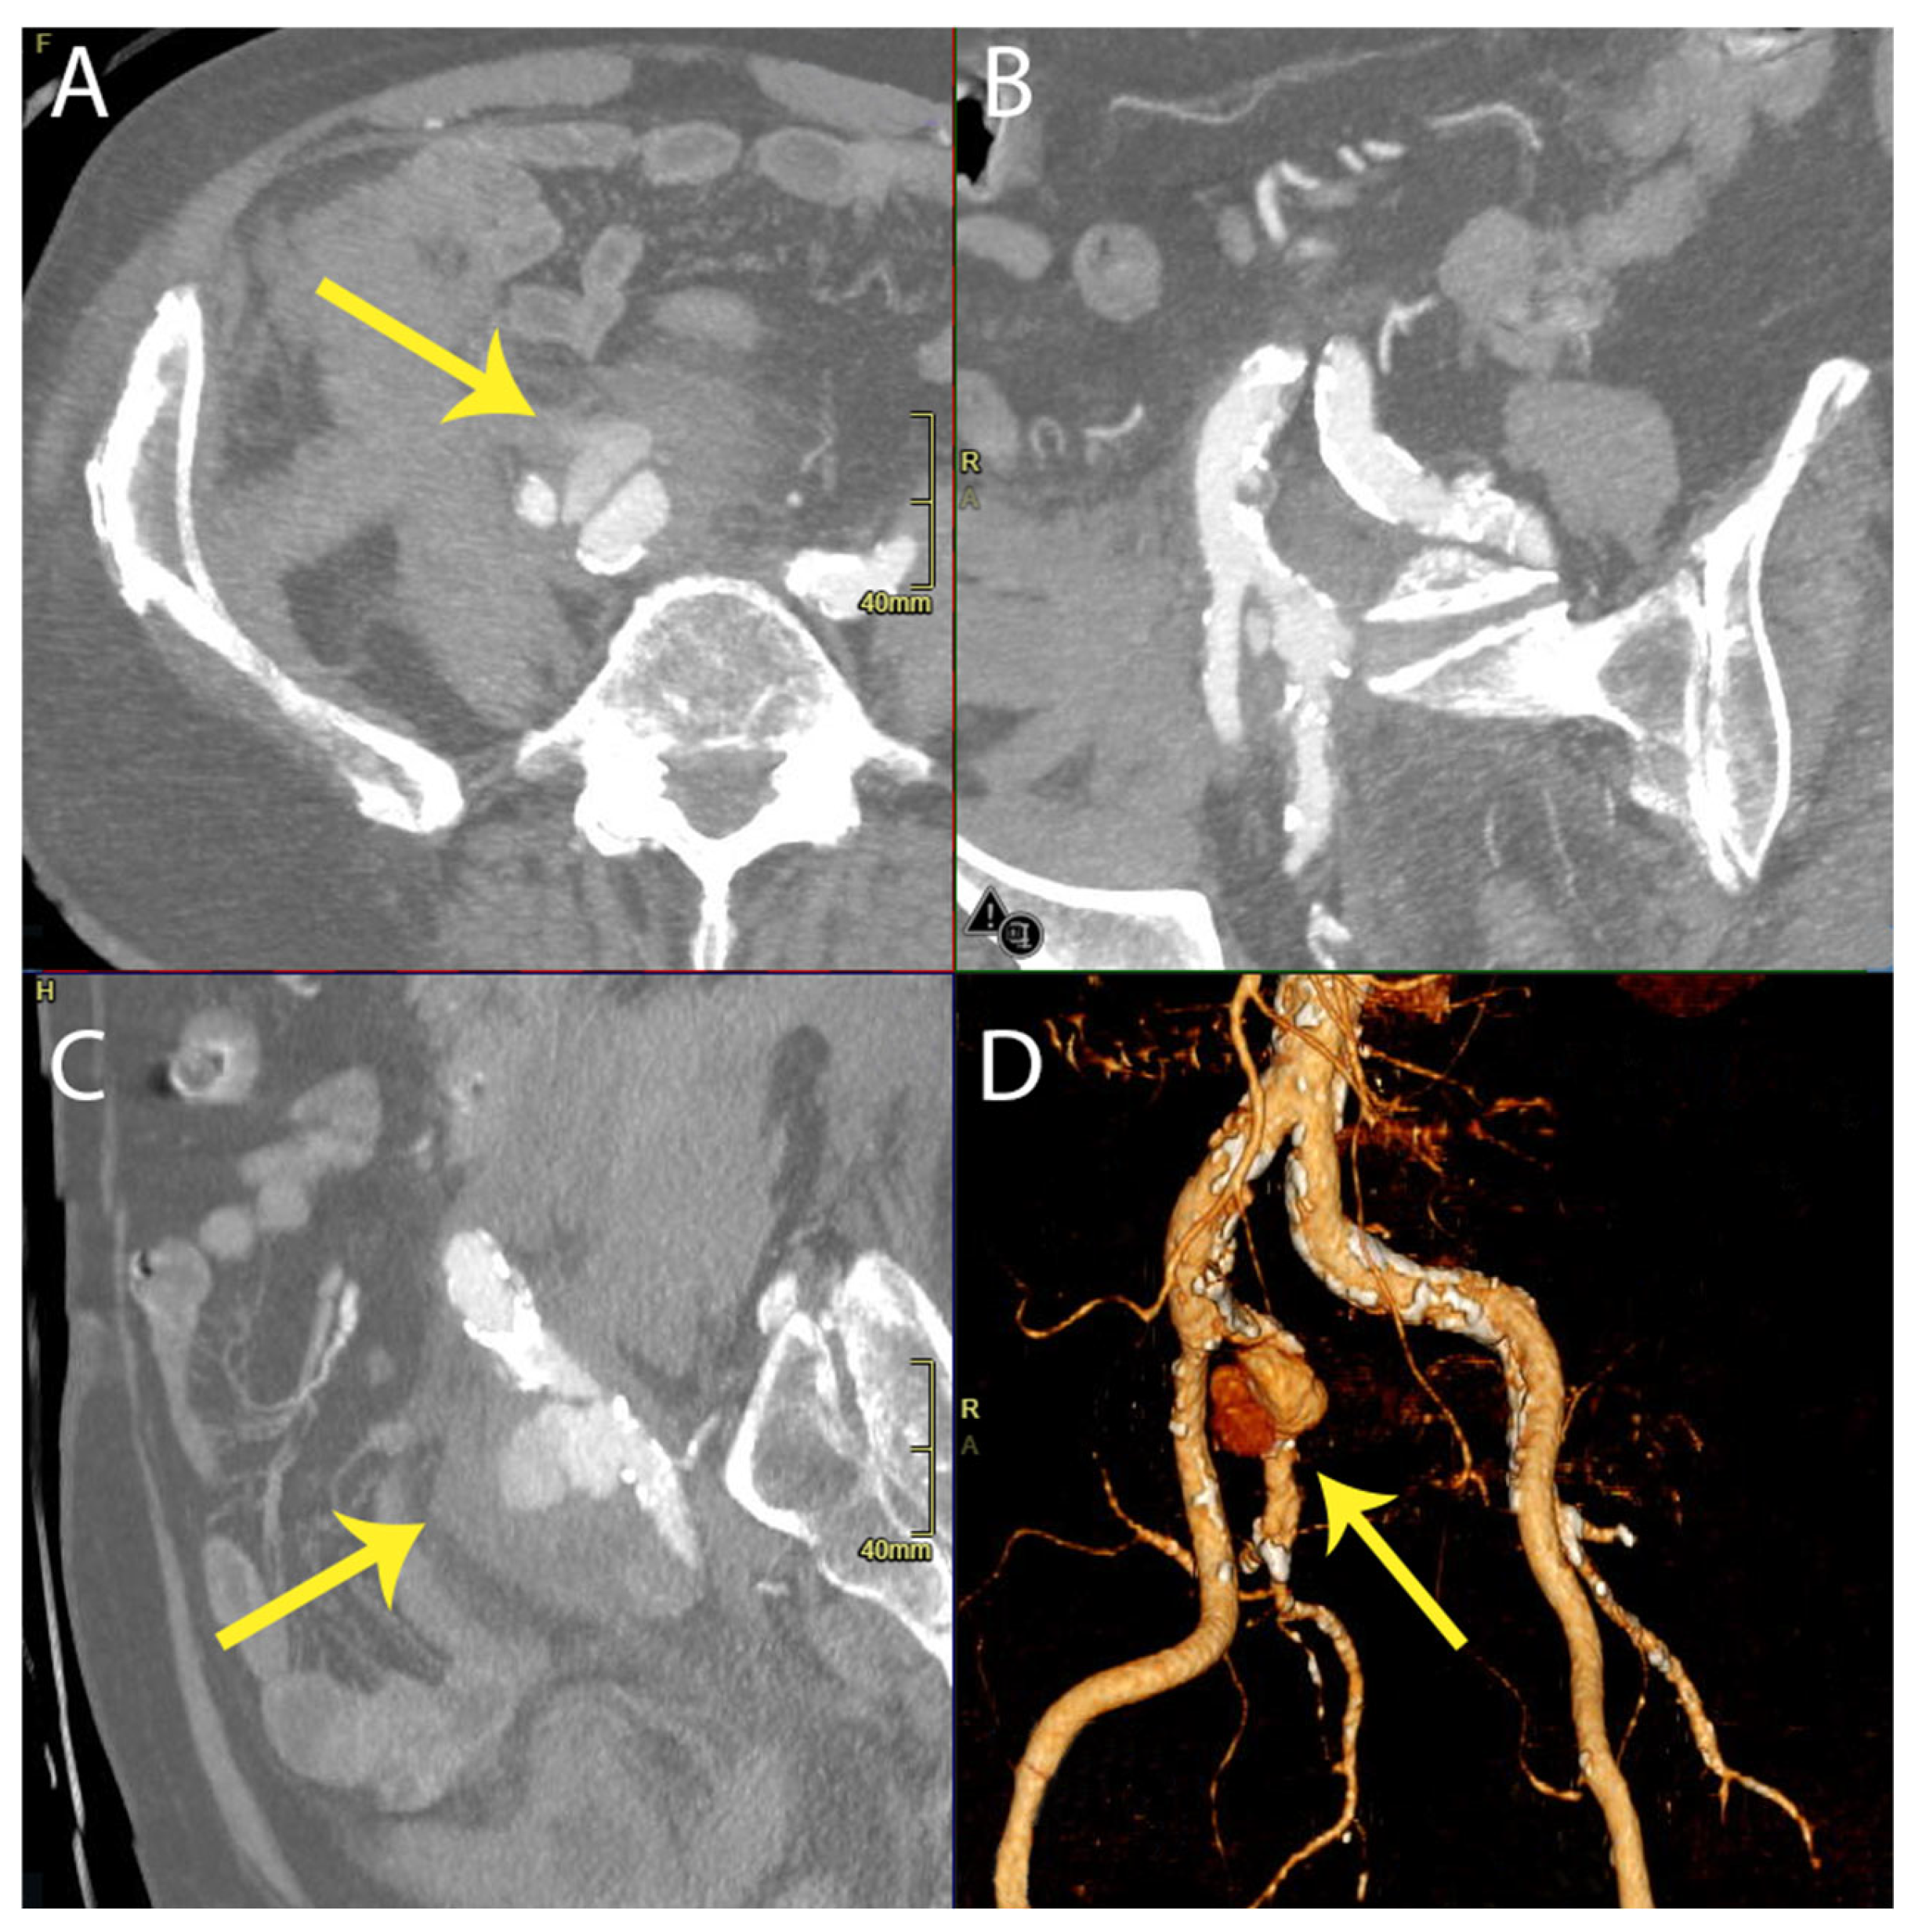

In our case, the presence of IIAA rupture, as indicated by preoperative CT angiography, led to the decision to proceed with an endovascular approach, considering the patient’s fragility. This strategy aimed to fully cover the IIA with an endograft. A review of previous CT scans from one month prior to the rupture event revealed no evidence of aneurysms; instead, only atherosclerosis of both iliac arteries and some ectasia of the right common iliac artery (with a maximum diameter of 18 × 20 mm) were noted, with the IIA measuring 13–15 mm in the portion that was most ectatic. See Figure 4.

Figure 4. Abdominal CT scan performed one month prior to the rupture event showed no evidence of aneurysms.